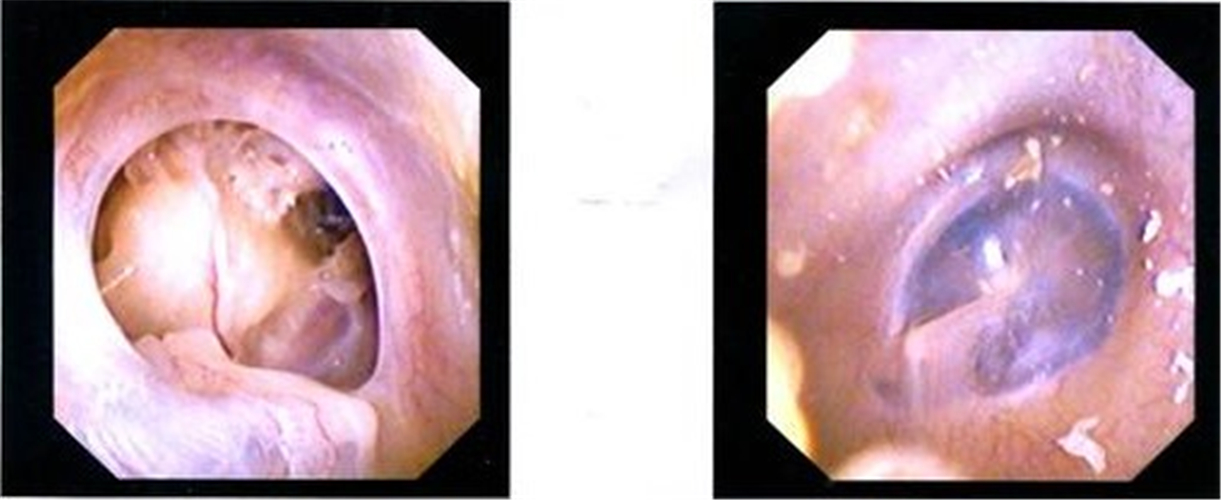

聊一聊鼓膜,蓝鼓膜

(1)急性期:鼓膜充血,内陷(光锥分散或消失,锤骨柄向后上方移位,锤骨